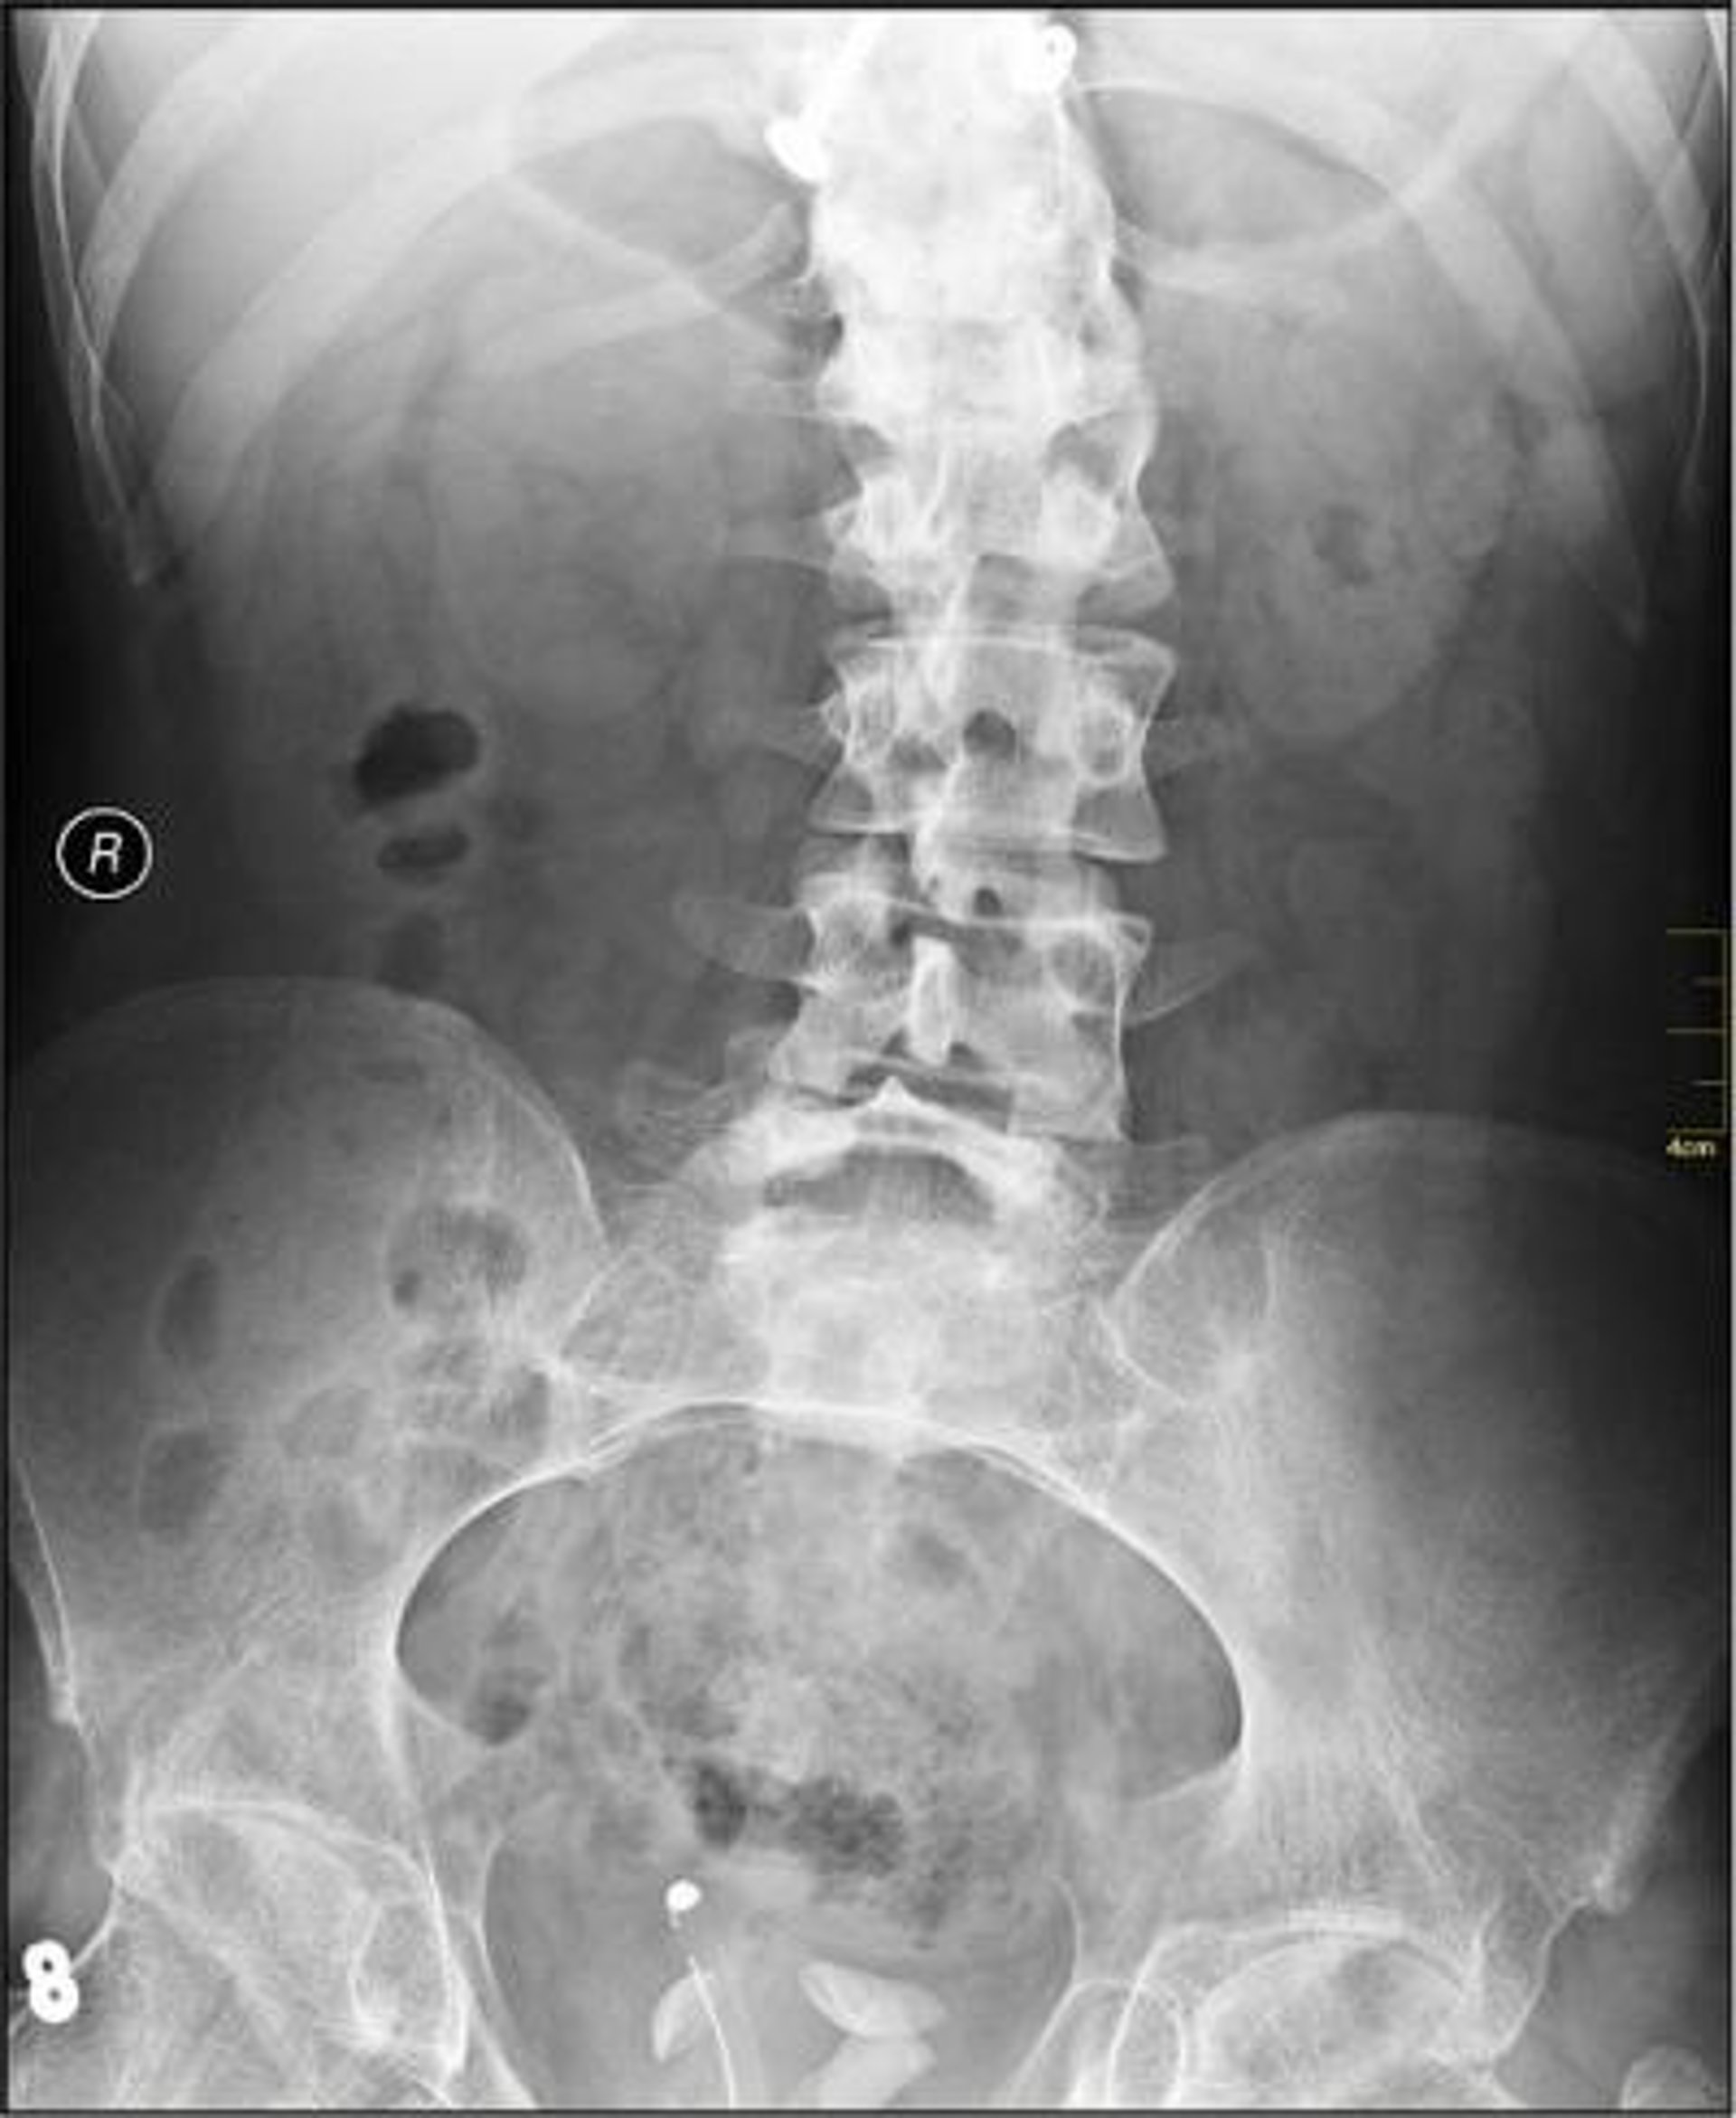

La monitorización de los adolescentes con escoliosis para saber cuándo llevan el corsé puede favorecer su uso y, con ello, frenar o retrasar la desviación de la columna vertebral y hasta evitar la cirugía, según los resultados de un estudio publicado en el 'Journal of Bone and Joint Surgery'.

El corsé suele utilizarse cuando el desvío de la columna vertebral está entre 25 y 45 grados, pero cuando no se usa de forma continuada no consigue los beneficios deseados, recuerdan los investigadores del Texas Scottish Rite Hospital for Children en Dallas (Estados Unidos) que han liderado el estudio.

La desviación media al inicio del estudio fue similar en ambos grupos al principio del estudio (33,2 grados en quienes sabían que llevaban sensores, 33,9 grados en los que no habían sido informados).

Asimismo, la curva de la columna vertebral no progresó más de 6 grados entre el inicio y el final del estudio en el 59 por ciento de los pacientes conocedores de los sensores, frente al 36 por ciento de los pacientes no monitorizados. Y al final del estudio, quienes acabaron necesitando cirugía habían usado el corsé unas 2,1 horas más que el resto.